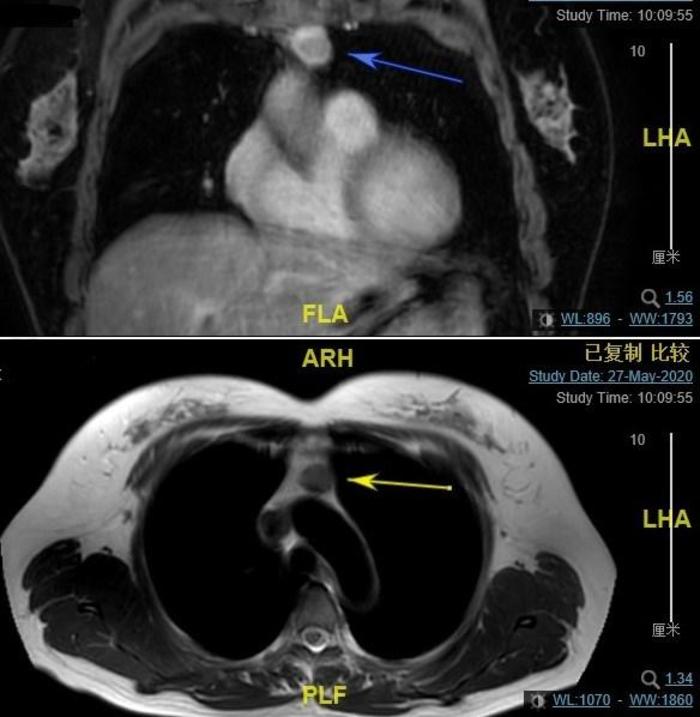

上图,磁共振可见肿瘤包膜完整。总体而言,术前考虑低度危险的胸腺瘤。

胸腔镜手术左进胸,切除肿瘤,见此肿瘤包膜完整。这是将来治疗效果好的一个预后指标。但是术后病理是B3型胸腺瘤(恶性胸腺癌)。